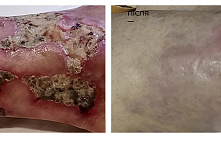

Трофічні виразки на ногах – дуже поширена патологія, особливо у людей старшого віку.